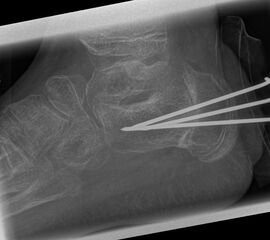

Zusätzlich schränken Wachstumsfugen die Wahl der Osteosynthese ein. Eine die Fuge kreuzende Osteosynthese ist ausschließlich mit Kirschner-Drähten möglich (Abb. 3).

Abb. 3 a-j: Beispiel einer Calcaneusverschiebeosteotomie mit offenen Wachstumsfugen und der entsprechenden Osteosynthese mit Kirschner Drähten. Lokalisation der Osteotomie (a), Lage der Fräse (b-d), Drahtlage mehrere Ansichten (e-h), Heilung der Osteotomie 4 Wochen postoperativ und Entfernung der Drähte (i-j).

Calcaneus-Osteotomie

Die minimalinvasive Calcaneusverschiebeosteotomie bietet eindeutige Vorteile gegenüber dem offenen Verfahren, sodass wir bei Kindern und Jugendlichen nahezu keine offene Verschiebeosteotomie mehr durchführen. Am Calcaneus liegt die offene Wachstumsfuge dorsal. Bei der Durchführung müssen Schenkel der V-förmigen Osteotomie daher etwas steiler angelegt werden, in einem stumpfen Winkel (siehe Abb. 3 a-j). Für die Osteotomie liegen unsere Patienten auf dem Rücken und der BV wird für die exakte Seitaufnahme eingestellt. Der Fuß lagert auf einem hohen OP-Kissen und die Osteotomie kann bequem mit einem langen Kirschner-Draht und einem sterilen Stift angezeichnet werden (Abb. 15).